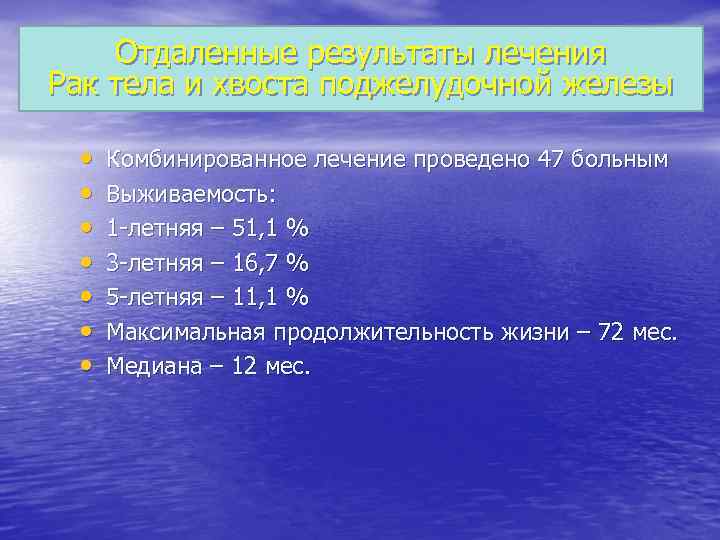

Отдаленные результаты лечения Рак тела и хвоста поджелудочной железы • • Комбинированное лечение проведено 47 больным Выживаемость: 1 -летняя – 51, 1 % 3 -летняя – 16, 7 % 5 -летняя – 11, 1 % Максимальная продолжительность жизни – 72 мес. Медиана – 12 мес.